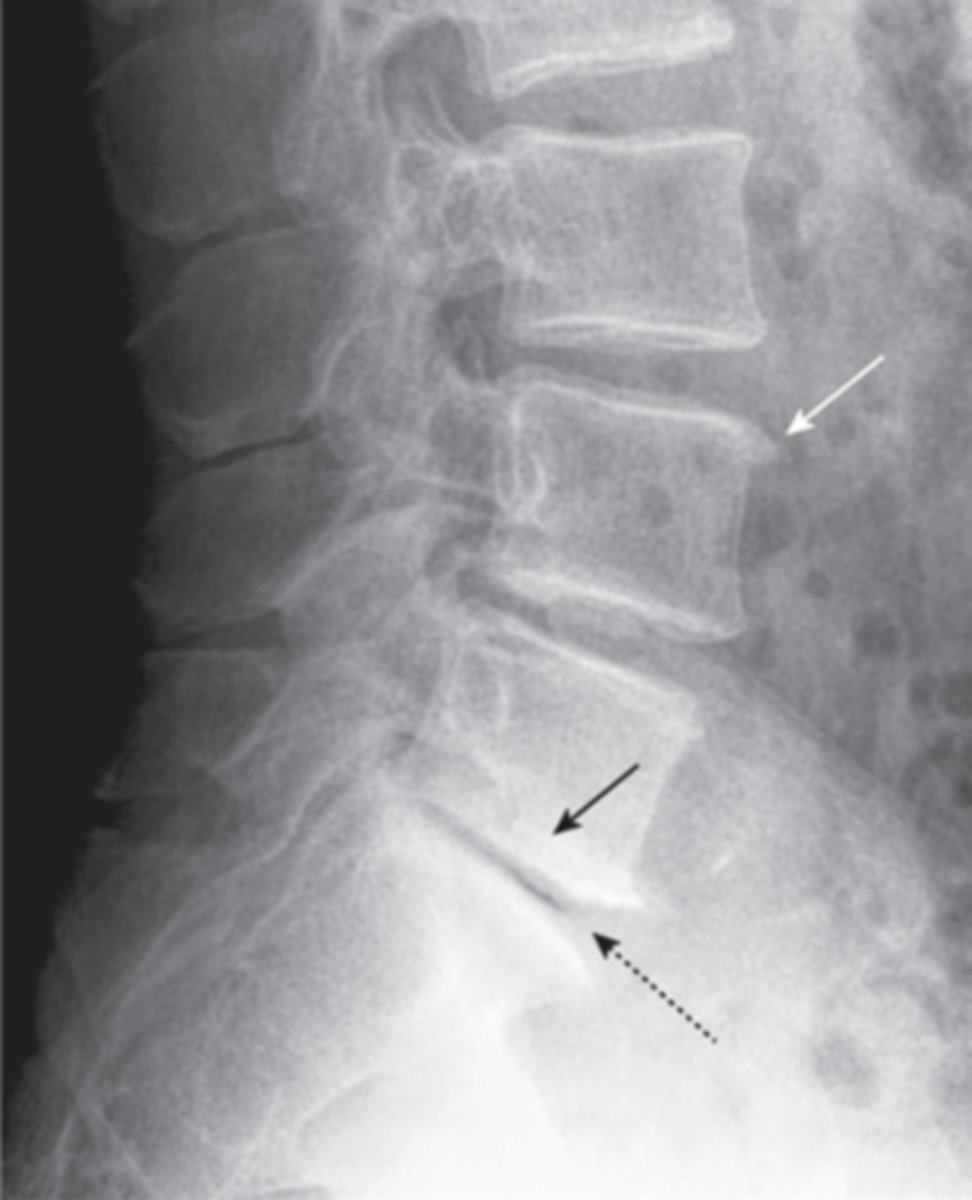

degenerative disk disease

progressive loss of height of the intervertebral disk space

- disk space narrowing

- vertebral body changes

- vacuum disk phenomenon- appearance of air density in disk space

herniated disks

degeneration of outer annular fibers, caused by acute compression of nerve root

MRI is study of choice

compression fractures

collapse of vertebrae, usually secondary to osteoporosis, no neuro deficit, wedge-shaped deformity

CT- best at identifying